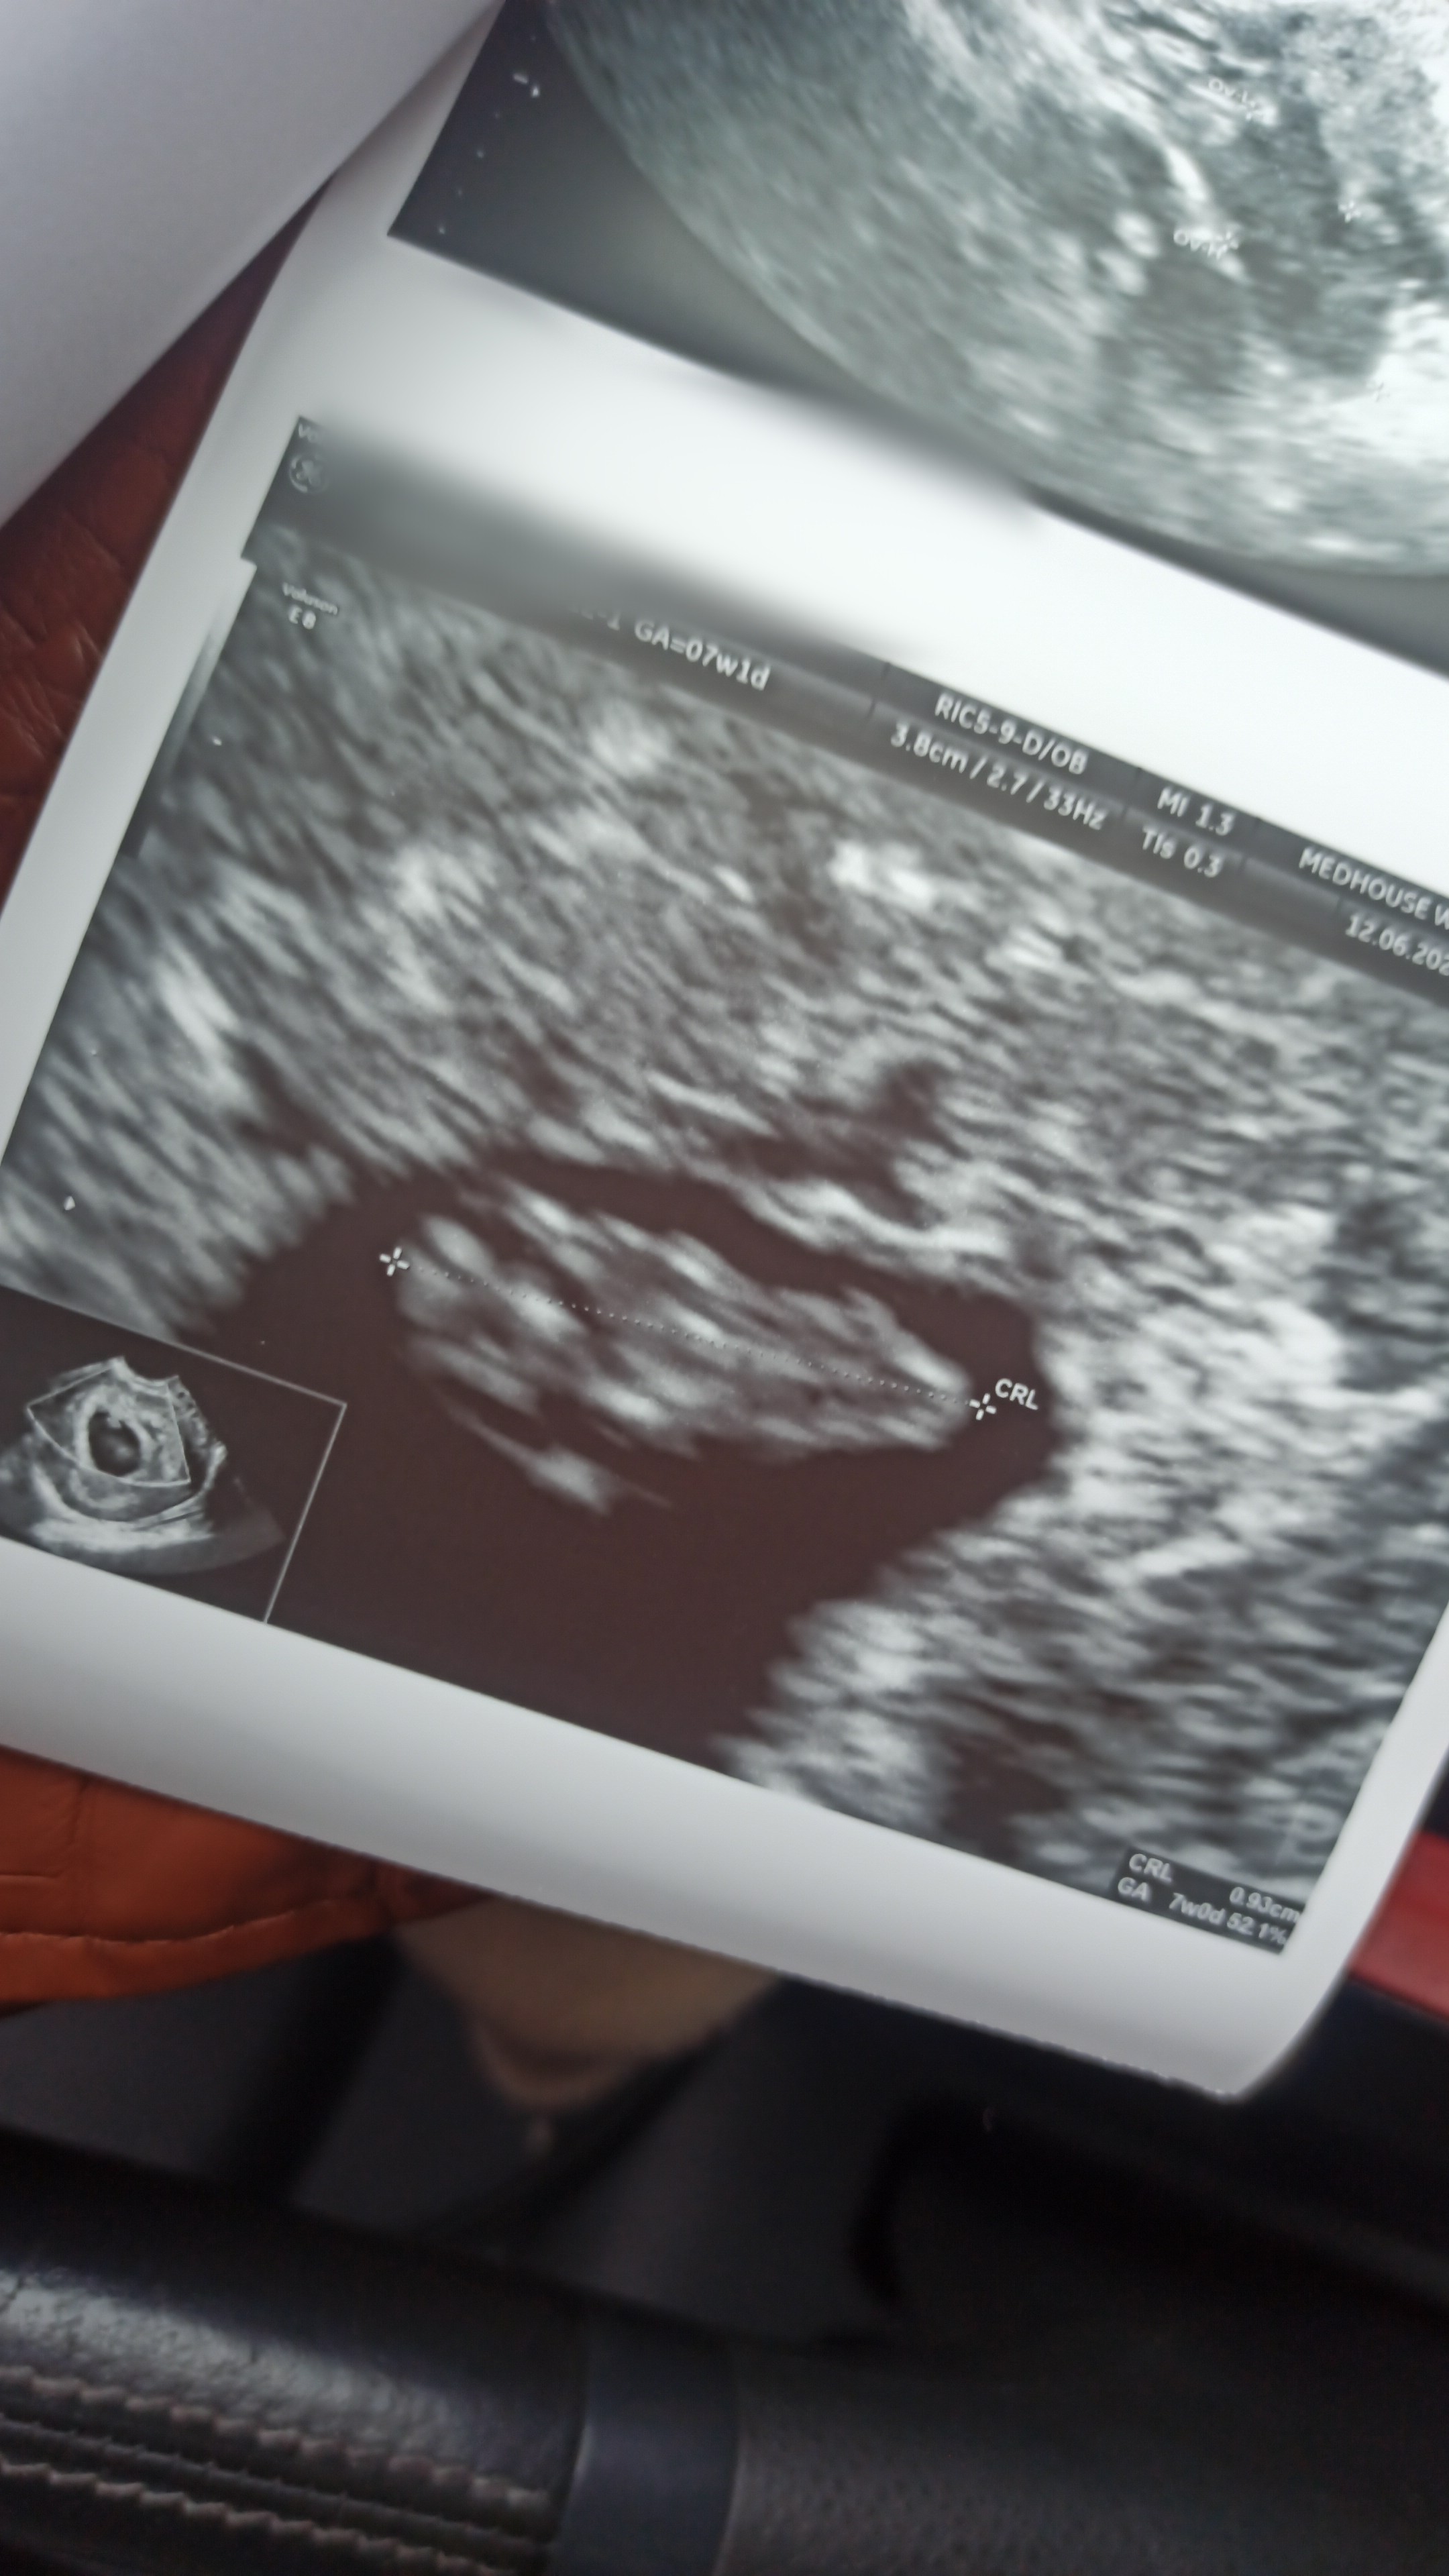

cudownieNie wytrzymałam do 19poszłam dziś na wizytę prywatna by upewnić się, że serduszko jest i ma się dobrze

więc oficjalnie serduszko puka, a wiek ciąży idealnie zgadza się z terminem OM

wow gratulacjeNie wytrzymałam do 19poszłam dziś na wizytę prywatna by upewnić się, że serduszko jest i ma się dobrze